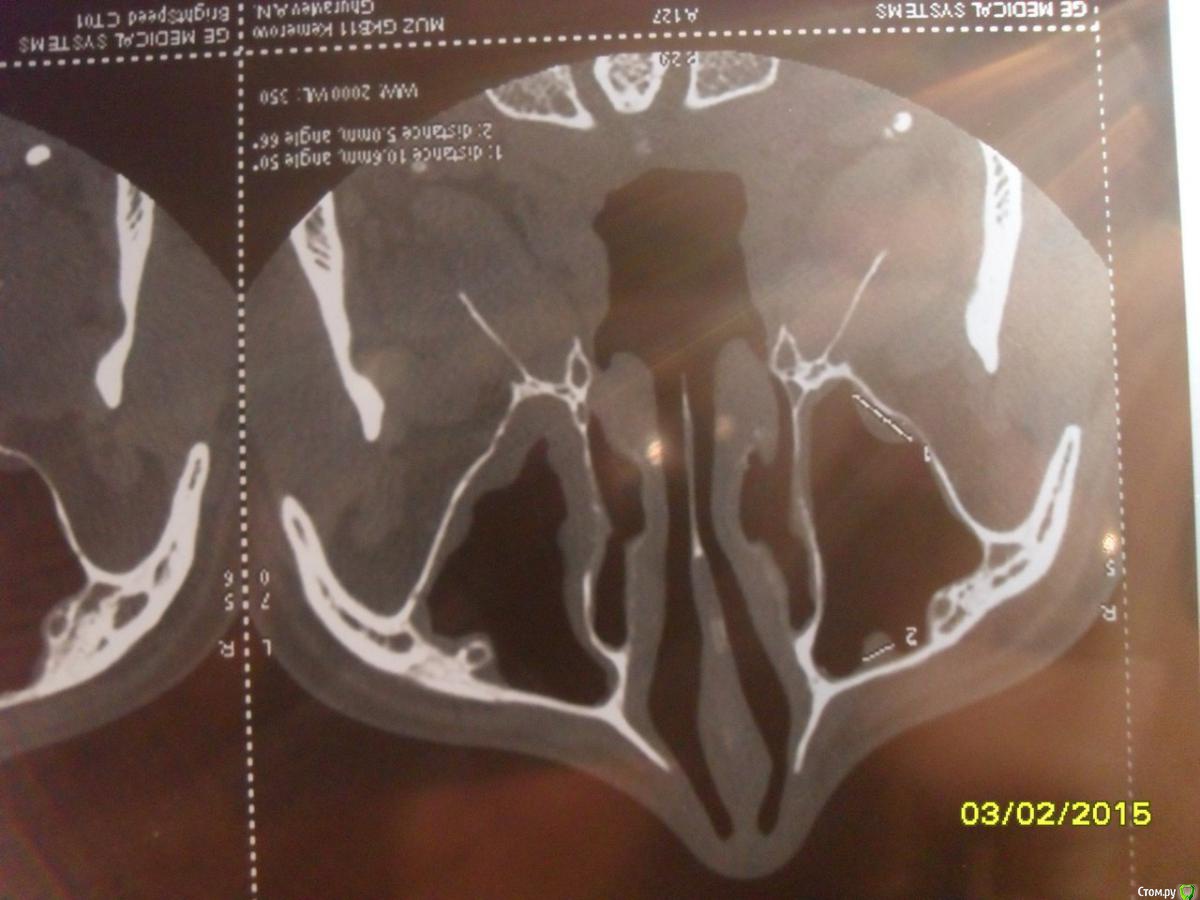

asin Опубликовано 7 февраля, 2015 Поделиться Опубликовано 7 февраля, 2015 (изменено) Добрый день всем, прошу у вас помощи или совета. Ездил на МСКТ пазух носа нашли пломбировочный материал, сломанный инструмент и кисту в правой пазухе 5 зуб. у меня его делали там штифт стоит канал пломбирован((((( мучает хронический катаральный гайморит((((( снимки прилагая может быть подскажите что мне делать.советуют дергать зуб с корнем и потом ушивать потому что откроется вход в пазуху....https://yadi.sk/d/nfWCumo7eU5ST тут образ диска МСКт... если кто то посмотрит буду признателен Изменено 7 февраля, 2015 пользователем asin Ссылка на комментарий

asin Опубликовано 28 апреля, 2015 Автор Поделиться Опубликовано 28 апреля, 2015 планируется операция 1.Операция на верхнечелюстной пазухе (с применением радионожа "Surgitron", бормашины, (эндоскопически ) - удаление пломб материала2. Подслизистая коррекция перегородки носа с применением радионожа "Surgitron" расширение левого соустья и прижигание слизистой отсюда вопрос, как сложно будет достать материал именно оттуда где он лежит? Ссылка на комментарий